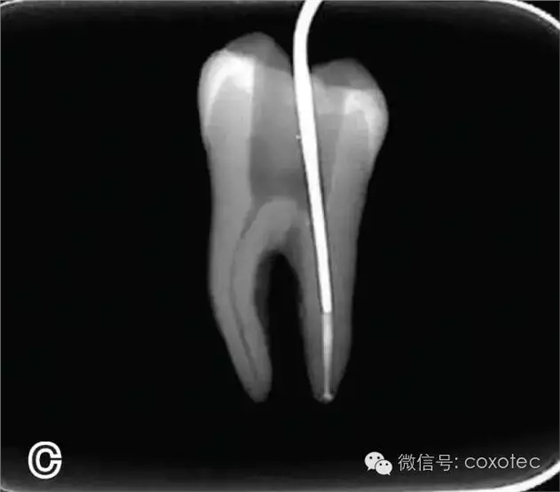

圖2 選擇垂直加壓器,A.試垂直加壓器 B.垂直加壓器在根內(nèi)的位置 選擇非標(biāo)準(zhǔn)牙膠尖(如0.04、0.06 錐度牙膠尖)作為主尖,型號(hào)一般與根管預(yù)備最大號(hào)的器械型號(hào)一致,能到達(dá)距根尖0.5~1 mm 處,主尖尖段與根管壁緊密接觸。拍試尖X 線片進(jìn)行確認(rèn)(圖3)。

圖3 試尖,A.試主尖 B.拍試尖X片